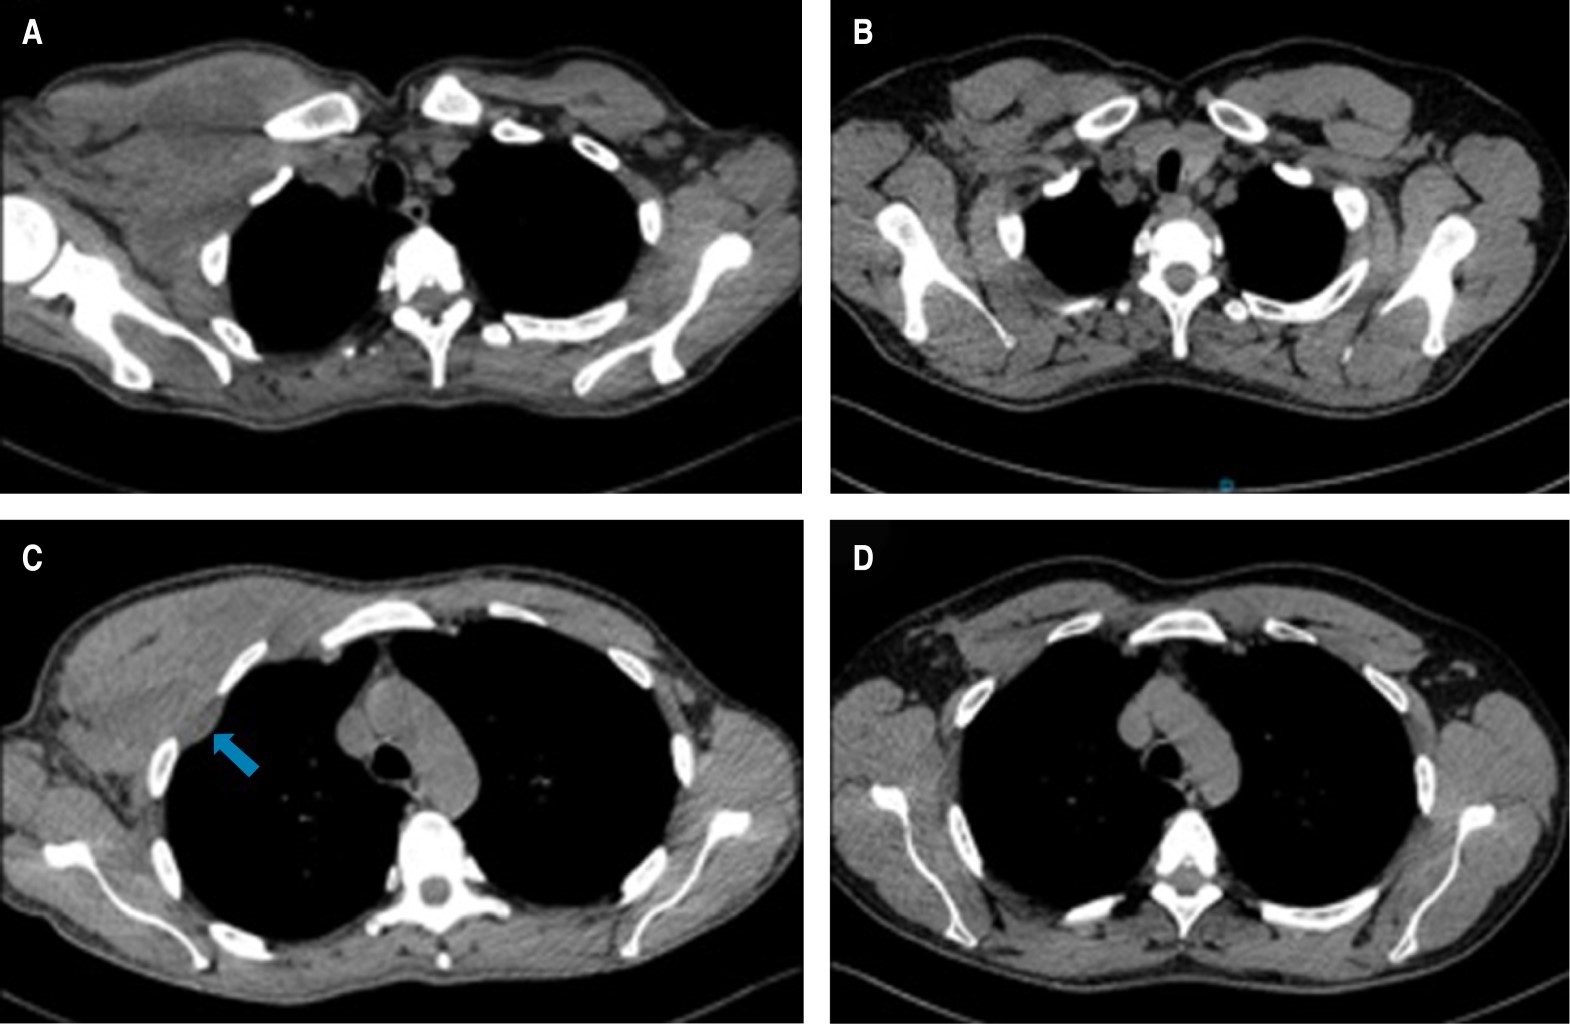

Debido a la localización, se envía al Servicio de Cirugía Cardiotorácica donde a la exploración se observa masa fija a pared torácica derecha, dolorosa a la palpación, principalmente en extensión hacia la axila, de consistencia firme y sin evidencia de circulación colateral en piel. Se valora tomografía de tórax contrastada donde se reporta tumoración de aspecto infiltrativo a nivel de tejidos blandos en región axilar derecha con arteria nutricia proveniente de arteria axilar, dicha lesión es irregular con dimensiones aproximadas de 8.8 cm en su eje cefalocaudal, 11 cm latero-lateral y 7.5 cm en su eje rostroventral, coeficiente de atenuación en fase simple de 20 unidades Hounsfield (UH) y al paso de contraste con captación de 37 UH. Dicha lesión no invade estructuras óseas adyacentes, únicamente se evidencia el desplazamiento de pectoral menor, subescapular y serrato anterior ipsilateral. En región axilar ipsilateral se identifican adenopatías de morfología redonda y captación significativa al contraste. Además, se identifican adenopatías que conservan su hilio graso prevasculares, pretraqueales e hiliares. Se concluye: tumoración infraclavicular/axilar derecha con infiltración a ganglios regionales adyacentes al mismo (Figuras 1 y 2). Es por esto que se toma biopsia con aguja de corte que reporta tejido fibroconectivo.

Un mes después del inicio de los síntomas, el paciente acude a consulta refiriendo reducción de la tumoración de forma espontánea, donde a la exploración física no se observa ni se delimitan masas a la palpación, por lo que se realiza tomografía de tórax en diferentes cortes donde no se observan remanentes de la tumoración torácica o de las linfadenopatías (Figuras 1 y 2).

Figura 2